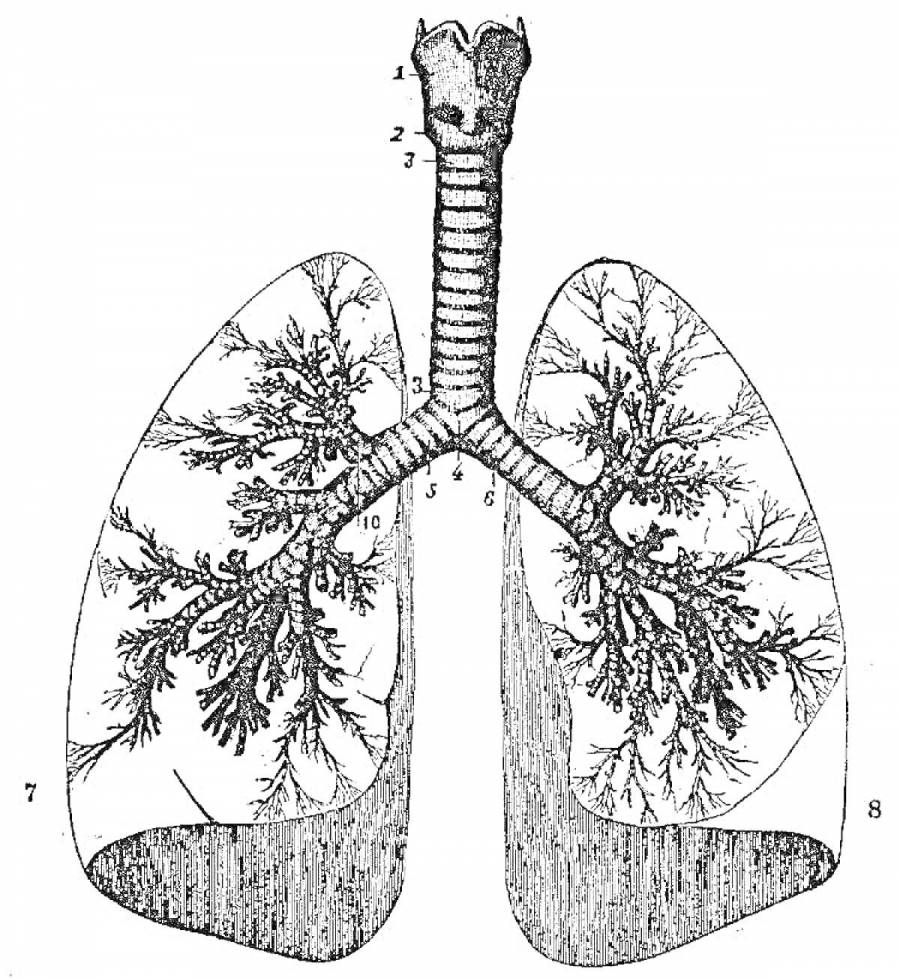

Здоровье дыхательной системы: бронхи и легкие

Раздел: Светлые идеи